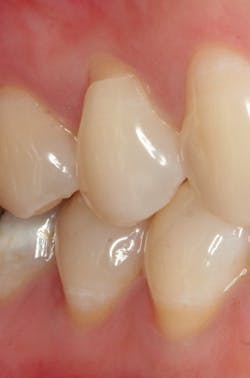

Figure 2: Non-carious cervical lesion commonly associated with abrasion, excessive occlusal forces, and a low pH.

Tooth wear is a process resulting from three primary factors-abrasion (from the interaction of teeth with other materials); attrition (from tooth-to-tooth contact); and erosion (wear after teeth come into contact with environmental or dietary acids) (see Figures 2-5). In addition, numerous behaviors and health factors contribute to the process of tooth wear, including, but not limited to: a diet high in acidic beverages and foods, bruxism, aggressive or improper tooth brushing, low pH of the oral cavity (acid reflux, GI disorders, bulimia nervosa) and oral hygiene habits.